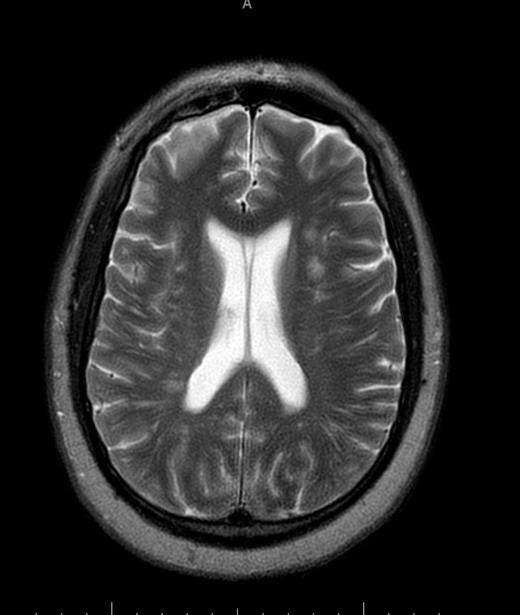

The variant sickle cell hemoglobinopathies have a variety of phenotypic presentations. Sickle cell beta plus thalassemia is an uncommon variant with an incidence that is 1/10th of sickle cell trait. This phenotype usually is associated with a milder clinical course, however often the first clinical presentation of such patients can be fatal vaso-occlusive crisis. Our case involves a 47 year old African American male with a reported history of sickle cell trait presenting with acute on chronic lower back pain for which an organic cause could not be identified with plain Xrays. He was treated with benzodiazepines and narcotics and later admitted to the ICU after being found unresponsive at home. He required intubation for airway protection. He was started on a Narcan drip for presumed narcotic overdose, without improvement. Noncontrast CT imaging of the head was negative. Laboratory findings were significant for anemia, thrombocytopenia, leukocytosis, acute kidney injury and elevated liver enzymes. Hemolysis was suspected with a markedly elevated LDH. Peripheral smear showed mild microangiopathic changes with 0-1 schisctocytes per hpf without evidence of sickle cells. Hematology was consulted and the patient was started on plasma exchange for a presumed diagnosis of TTP, however it was discontinued when his ADAMTS13 returned at a low-normal 67%, and TTP was felt less likely. MRI of the brain showed multiple focal and patchy areas infarcts throughout white matter of both cerebral hemispheres. MRI of the lumbar and thoracic spine showed a heterogeneous appearance of the bone marrow, concerning for a marrow infiltrative process. Work up for infectious or vasculitic causes were unremarkable. Hemoglobin electrophoresis showed Hb A1 20.2 (L), A2 5.8 (H), Hb F 2.2 (H), Hb S 71.8 (H), identifying doubly heterozygous sickle cell beta plus thalassemia. Bone marrow biopsy was hyperplastic with areas of geographic necrosis with sickle cells causing sludging and congested sinusoidal spaces suggesting ischemic necrosis due to vaso-occlusion. He was treated with exchange transfusion, with repeat hemoglobin electrophoresis showing A1 73.2 (L), A2 3.5 (H), HbS 23.3 (H). His lupus anticoagulant was positive raising concern for APLAS contributing to his catastrophic clinical course and severe neurologic disease,so he was started on anticoagulation with Lovenox and high dose steroids at a dose of 1 mg/kg daily. When the anticardiolipin and beta2 glycoprotein antibodies returned negative, the steroids were tapered and eventually discontinued. The clinical significance of the lupus inhibitor remains unclear. Shortly after initiation of plasma exchange and simple transfusion, the patient did stabilize hematologically. Platelets returned to the normal range and there was no evidence to suggest ongoing hemolysis. Renal and liver function improved. However he made no neurological recovery. He continued to require ventilator support and underwent a tracheostomy. A repeat MRI head showed progressive infarcts of both cerebral hemispheres, with new cerebellar infarcts. He was declared brain dead after 23 days and care was withdrawn. This case demonstrates that sickle cell beta plus thalassemia can present with acute hemolysis and bone marrow necrosis in otherwise healthy adults. The literature supports bone marrow necrosis and subsequent fat emboli as the likely pathophysiologic nidus responsible for multiorgan system failure including the catastrophic neurologic insult in this patient. Prompt recognition of this uncommon and challenging disease presentation and timely treatment with exchange transfusion may lead to improved clinical outcomes.